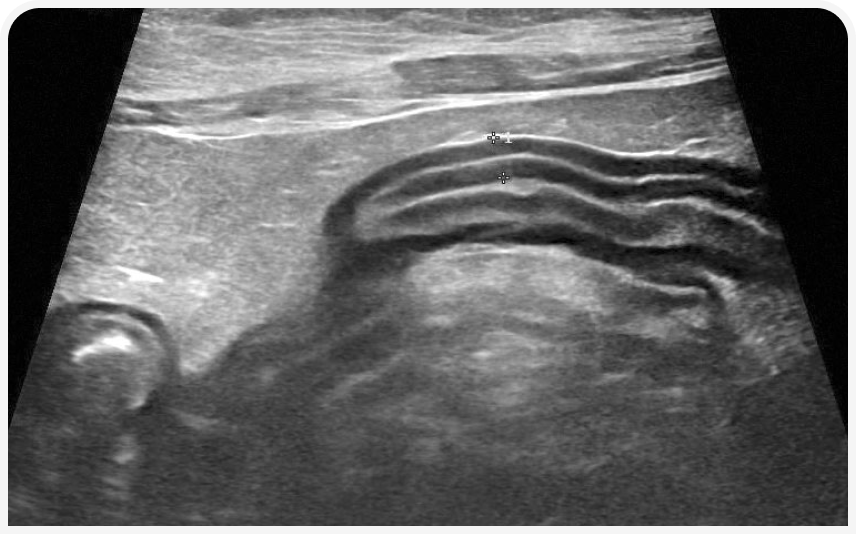

По мнению автора, у кошки с потерей веса невыясненного происхождения часто очень информативным для диагностики оказывается ультразвуковое исследование органов брюшной полости. Особенно внимательно исследуют желудочно-кишечный тракт, определяя общую толщину стенки различных отделов кишечника и соотношение толщины слизистой оболочки и мышечного слоя. Как правило, требуется дообследование любых сегментов тонкой кишки с толщиной стенки > 3 мм; на патологию также может указывать увеличение толщины мышечного слоя (19). Диффузное утолщение мышечного слоя иногда наблюдается у клинически здоровых кошек, но чаще — при ВЗК или инфильтративных заболеваниях желудочно-кишечного тракта, таких как мелкоклеточная лимфома и гистоплазмоз (Рисунок 3).

Ультразвуковое исследование позволяет обнаружить и другие проявляющиеся только незначительным дискомфортом и вызывающие вторичную гипорексию поражения органов брюшной области, такие как хронический панкреатит, хотя подобные малозаметные изменения эхогенности трудно оценить корректно, не имея высококачественного аппарата или значительного опыта специалиста (Рисунок 4) (16). При ультразвуковом исследовании легко выявить поражения почек (например, обструкцию мочеточника или гидронефроз), нередко вызывающие хронический дискомфорт, достаточно выраженный, чтобы нарушить потребление пищи (20). Если контралатеральная почка не поражена, уровень креатинина в сыворотке крови и удельный вес мочи будут находиться в пределах референсного интервала.